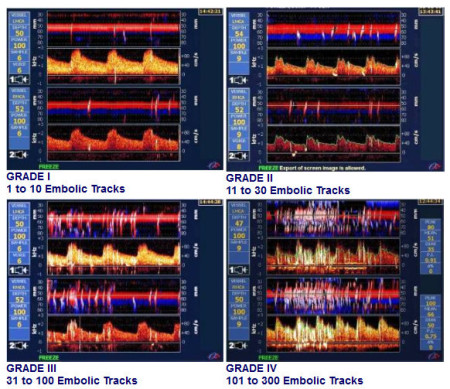

"Bin ich dicht?" Der Bubble-Test

Der erste und einfachste Schritt ist ein sogenannter "Bubble-Test". Dabei wird ein gut verträgliches und sicheres Ultraschall-Kontrastmittel (z.B. Echovist oder agitierte Kochsalzlösung), das winzige Gasbläschen ("Bubbles") enthält, in eine Armvene gespritzt, zumeist rechts. Das Ultraschall-Kontrastmittel fließt dann über die Venen in das rechte Herz. Ist die Trennwand zwischen dem rechten und dem linken Vorhof durch ein PFO – oder aber durch einen anderen Defekt – nicht ganz verschlossen, kann das Kontrastmittel aus dem venösen Kreislauf in das arterielle Gefäßsystem übertreten. Die Gasbläschen ("Bubbles") werden mittels Doppler-Sonographie registriert und sind an den großen Zacken und Ausschlägen im Dopplerbild zu erkennen.

Mit dieser Methode kann man also zunächst feststellen ob überhaupt ein "shunt" besteht. Ist dem so, bezeichnet man den Bubble-Test als "positiv". Positiv ist jedoch nicht gleich positiv! Es kommt darauf an, wie viele Bläschen übertreten und unter welchen Bedingungen. Wenn viele Bläschen in Ruhe "shunten" geht man von einem anatomisch offenen PFO aus. In diesem Fall ist "die Tür nicht nur angelehnt", sondern steht offen. Treten Bläschen nur nach Pressen durch das Valsalva-Manöver (forcierter Druckausgleich) über – geht man von einem sogenannten "funktionell offenen PFO" aus – dann wäre die Türe tatsächlich nur angelehnt und öffnet sich lediglich unter Druck.

Je nach Größe und Menge der übertretenden Blasen teilt man ein PFO in drei verschiedene Grade ein. Die Gradeinteilung – abhängig von Größe und Anzahl der übertretenden Blasen sowie dem Vorhandensein von Kofaktoren wie z.B. einem Vorhofseptumaneurysma (Aussackung der Vorhofscheidewand) – ist wichtig für das gesundheitliche Risiko an Land und die damit empfohlenen therapeutischen Maßnahmen – und für Taucher natürlich für die eine wichtige Frage: die zukünftige Tauchtauglichkeit.

Da ein Zusammenhang zwischen der Shunt-Größe beim PFO und dem Risiko für eine Dekompressionserkrankung (aber auch für einen Schlaganfall) nachgewiesen wurde, spielt die Erfassung des Shunts für die weitere Therapie eine große Rolle: Bis zu 5 "Bubbles" in einem einzigen echokardiographischen Standbild gelten als kleiner, 6 bis 25 "Bubbles" als mittlerer und mehr als 25 "Bubbles" als großer Shunt. Eine Häufung von Schlaganfällen und Dekompressionserkrankungen wurde vor allem bei Shunts oberhalb von 20 "Bubbles" festgestellt, und zwar traten diese zum Teil trotz gerinnungshemmender Medikation auf.